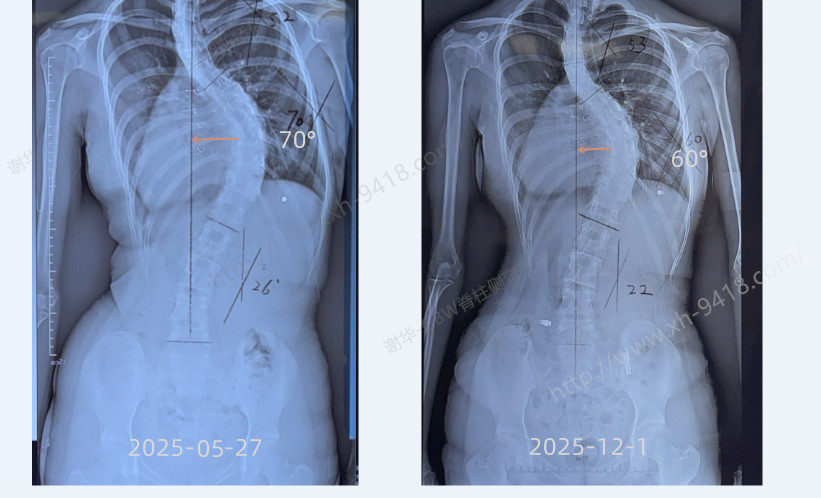

2025年5月底,这位16岁的女孩在最初来我们重庆工作室时,胸段主弯已达到70°,侧弯非常严重,脊柱僵硬,体质较差,瘦弱且无力,刚开始进行施罗斯体操矫正时,做些常规的训练动作都很困难,矫正难度较大。为了改善她的脊柱状况,她开始佩戴GBW型支具,并且坚持每周三次在治疗师的指导下进行施罗斯体操锻炼。

经过六个多月的努力,她的情况得到了显著改善:主胸弯度数减少了10°,顶椎更贴近身体中线;剃刀背下降了12°,整体体形也有了很大改善。这些成果的背后,是她和家人对矫正过程的坚持与支持,同时也证明了施罗斯体系的有效性和科学性。

X片对比情况:顶椎更靠近中线